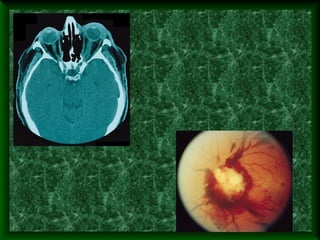

Thyroid eye disease. The patient is a 63-

year-old man with advanced thyroid-

related optic neuropathy. The presenting

visual acuity was 20/80 and 20/100,

respectively. A, External photograph with

marked bilateral chemosis. B and C,

Bilateral disc swelling with choroidal

folds emanating from optic disc. D,

Axial computed tomography scan showing orbital apex

congestion bilaterally secondary to marked muscle enlargement

(arrows). The patient underwent bilateral orbital radiation and

orbital decompression. Final visual acuity was 20/40 in each eye.

Нейропатия при

гипертериозе.